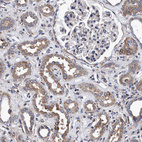

Immunohistochemistry analysis in human testis and pancreas tissues using HPA022989 antibody. Corresponding CALCOCO2 RNA-seq data are presented for the same tissues.